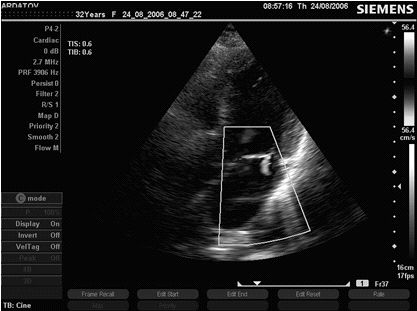

Диагностику ПМК нельзя основывать только на данных допплеркардиографии - следует учитывать распространенность незначительной митральной регургитации (рис. 9)

Рис. 9. Митральная регургитация I ст. в начале систолы при отсутствии видимых изменений створок клапана, режим ЦДК в апикальной проекции (собственное наблюдение).